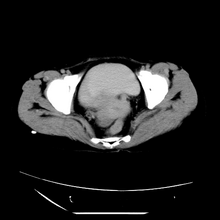

女性,41岁,发现左腹部包块3年,现行ct检查,检查前做过静脉肾盂造影。

左侧低密度区是脂肪密度,中间可见条索状软组织样密度影,现主要想知道左肾前下缘圆形软组织样密度影,内见低密度水样密度影,这是什么?

脾脏增大,左肾后方脂肪增多,脊柱前方脂肪增多,左肾窦脂肪增多,左肾变形,双肾积水以左侧为著,左肾内侧及上方见环形软组织肿物影,内部低密度区,考虑1盆腹腔/腹膜后及左肾窦脂肪增多症2左肾内侧病灶可能为左肾上腺病灶,可能为脂肪增多的原凶

1)考虑左肾替代性脂肪瘤病;不排除左肾错构瘤。2)双肾积水。

诊断rsl的必备条件是肾窦、肾门的脂肪组织增生和肾实质的萎缩,而且本例因为ivp后扫描不好判断有无肾结石但可能性较小;另外,占位效应显著,脾后缘都受压了,肾门以下肾实质残缺,支持肾脏错构瘤.

1、考虑左肾替代性脂肪瘤病,2、双肾积水,3、距脾,4、楼主说的我考虑为感染性病灶。